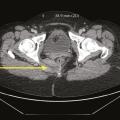

Tableaux et figures